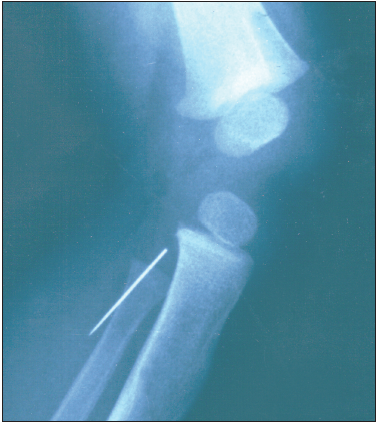

Radiographs were ordered by Anatoly Belilovsky, MD, of Brooklyn Hospital and Michael LaCorte, MD, of Schneider Children's Hospital in Brooklyn, NY. To everyone's surprise, the films revealed a sewing needle in the subcutaneous tissue. The child's mother did not sew at home; however, sewing needles had been present at the grandmother's home where the infant had crawled about on his hands and knees.

A repeated examination of the child's knee revealed no sign of an entry wound; there was no ecchymosis, no tenderness, and no local reaction, and the lesion still appeared soft and yielding on palpation with some crepitus.